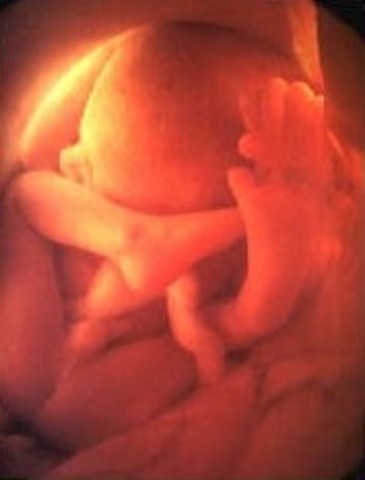

• Week 27

Week 27

This is the start of the third trimester and the look of the baby will be the same at birth. The brain is rapidly growing, and the retina of the eyes are developing.